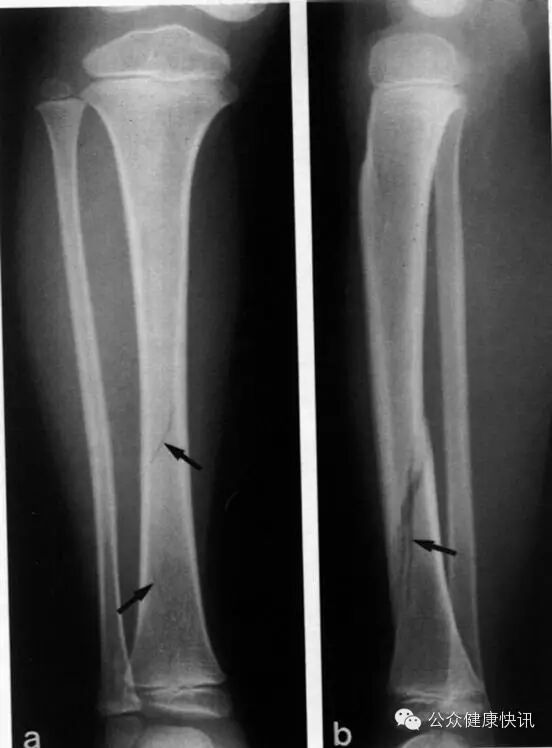

这是小孩子胫骨骨折的X线检查片子

3、骨、关节X线检查

骨、关节X线检查:主要用于骨折,炎症性和退行性骨、关节病、化脓性骨髓炎,骨、关节肿瘤、结核,脊椎形态改变的诊断。

特长:用于肺部疾病的基础诊断,比如肺炎,肺癌,支气管扩张等。在骨骼类诊断,比如骨折和各种骨类肿瘤,具有很大优势。另外对检查肠梗阻和大部分的肾结石也有很大的帮助。